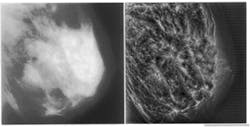

The complexity of a reconstructed mammogram can be reduced by selecting a subset of features that satisfy certain geometric constraints. An illustration would be choosing to focus on only those features oriented in a particular direction. Subsequent image reconstructions can then use the context provided by previously enhanced features to investigate additional characteristics that emerge at other scales and orientations (see Fig. 2). For example, fine vertical features can be selected and analyzed in the context of previously classified large horizontal features. Thus, the strategy provides a global context in which subtle features within finer scales might be classified incrementally through a precomputed hierarchy of scale-space.

FIGURE 2. Subtle structural features around a spicular mass are not visible in unprocessed mammogram (left). Multiscale processing using a nonseparable, nonorthogonal analyzing function reveals

calcifications and penetration of fibroglandular structures into the obvious mass tissue (right). The geometric shapes of the calcifications are seen more clearly, as are the ductules and arterial structures.